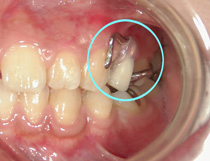

あとは、入れ歯の金具(バネ)が目立たないように設計したミニ入れ歯=写真右=を、技師の大西さんと打ち合わせを重ねて製作しました。

その結果、審美的にも問題のない優れた入れ歯に仕上がりました=写真。